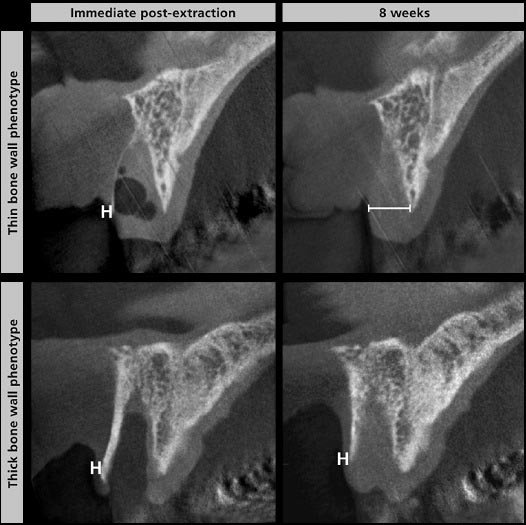

En los pacientes, luego de un extracción dental, es importante evaluar el espero de la pared ósea remanente, existen biotipos, por ejemplo un espero por debajo de 1 mm corresponde a un fenotipo de pared ósea delgada (Januario et al. 2011), dentro de las 8 semanas de cicatrización, estos fenotipos óseas de pared óseas delgadas revelan una pérdida media de hueso vertical de 62.3% o 7.5 mm (Chappuis et al. 2013). Se han hecho intentos para preservar la altura de la pared ósea para la futura colocación del implante inmediato (Araujo et al. 2005), colocación inmediato de injertos (Araujo et al. 2015), o mediante el aumento de la placa ósea facial (Favero et al. 2015).

Chappuis V, et al. realizaron un estudio prospectivo que fue la primera en su tipo para investigar la interacción entre las dimensiones de los tejidos blandos y la anatomía ósea subyacente durante un período de cicatrización de 8 semanas luego de la extracción dental de dientes anterosuperiores. El análisis se realizó mediante impresiones digitales y tomografía computarizada cone beam en el cual se realizó superposiciones de modelo de los tejidos blandos y óseos, el procedimiento se realizó inmediatamente luego de la extracción dental y a las 8 semanas de cicatrización. Se evaluaron dos fenotipos de tejidos blandos el delgado y el grueso. El grosor del tejido blando en fenotipos delgados y gruesos de hueso en la extracción fue similar, con un promedio 0,7 mm y 0,8 mm, respectivamente. Curiosamente, los fenotipos de hueso delgado revelaron un aumento de 7 veces más en el espesor del tejido blando después de un periodo de curación de 8 semanas, mientras que en los fenotipos de huesos gruesos, las dimensiones de los tejidos blandos se mantuvo sin cambios.

Fig. 2. Medición del espesor de tejido blando facial en fenotipos óseos delgados y gruesos basado en la tomografía computarizada de haz cónico (CBCT) imágenes a la extracción y después de 8 semanas de la curación.